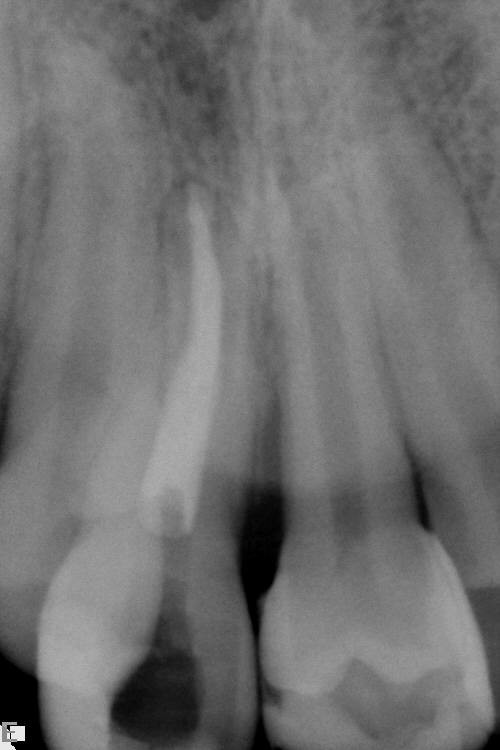

Tooth transplantation is a useful technique in a small number of clinical situations. For example, transplantation has been advocated to reposition ectopic canines, to replace developmentally absent teeth or to replace a tooth lost following trauma or pathology. In most of these scenarios there are other, often more appropriate treatments but in recent years there has been renewed interest in tooth transplantation to replace upper incisors lost following trauma. The most commonly affected are the upper anterior segment incisors, lost either due to root fracture, periapical infection, ankyloses, or external/internal root resorption (Figure 21).

The technique can be used for any ectopic teeth, such as canines, where a decision has been made to undertake transplantation rather than orthodontic alignment. Teeth should be transplanted just prior to, or on the completion of, root formation, ideally when there is still an open apex. In these situations, there is the possibility of revascularization and possibly re-innervation of the transplanted tooth.

Preoperatively space is created orthodontically (Figure 22). A socket is prepared to accept the tooth using burrs with water irrigation to prevent the bone overheating and subsequent necrosis (Figure 23). If further future eruption would be beneficial (for example in a growing patient) then again, care should be taken to prevent damage to the cementum, otherwise ankylosis may occur which would prevent further eruption.

If the apex of the tooth was closed prior to transplantation then a root filling should be placed immediately. If however the apex was open at transplantation then there is still the possibility of revascularisation of the pulpal tissue. In this situation, the tooth should be reviewed using the same protocol as would be used for an avulsed (knocked out) incisor. This involves the assessment of the tooth’s colour, colour when viewed with trans-illumination, pulpal vitality (response to electrical or thermal testing) and radiographic appearance. Obviously if there is evidence of pulpal necrosis, then the pulpal tissue should be extirpated and root canal therapy instigated (Figure 25). Once good healing of the periodontal ligament has occurred and the tooth is quiescent then appropriate restorative treatment can be undertaken to improve aesthetics.